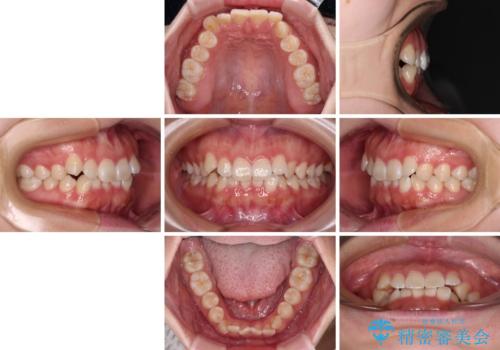

前歯のデコボコを整える インビザラインによる矯正治療

- 上下前歯のデコボコを気にして来院された患者様です。

叢生は軽度であり、ワイヤー矯正でもマウスピース矯正でも対応可能であったので、好きな装置を選んでもらいました。

相談の結果、インビザラインによる矯正治療を行うこととしました。

毎日の装着時間をしっかりと守っていただいたことで、1年程度で無事に治療を終えることができました。